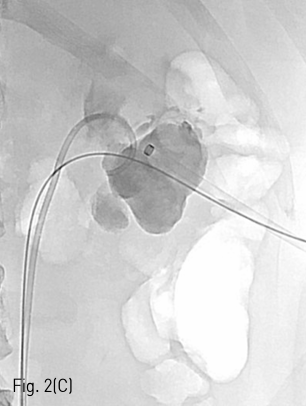

환자는 왼쪽 신장의 isolated calyx에는 8.5Fr. drainage catheter가 insertion 되어 있고 left renal pelvis에는 double J stent가 insertion 되어 있는 상태로 prone position을 취하였다. 기존의 drainage catheter에 0.035inch 유도 철사(Terumo, Tokyo, Japan)를 insertion 하고 catheter는 제거한 후 8Fr. Sheath(Boson, Shrewsbury, USA)를 삽입하였다. 조영제(Visipaque, GE healthcare, Chicago, USA)를 주사하여 tubogram을 시행하였고 isolated calyx 와 콩팥깔때기와의 연결성은 없었다. (Fig.1B) 초음파 유도 하에 21G 천자바늘(Cook, Bloomington, USA)로 isolated calyx를 천자하고 X선 투시하에 천자바늘을 콩팥깔때기에 insertion 되어 있는 double J catheter를 향해 진입시켰다. (Fig. 2A, B) 천자바늘의 속심을 제거한 후 X선 투시하에 조영제를 주사하여 isolated calyx를 지나 콩팥깔때기가 천자된 것을 확인하고 0.018inch 유도 철사(A & A, Gyeonggi, Korea)를 넣었다. (Fig. 2C) 이후 천자바늘을 제거하고 단일 막대 접근 장치(yellow sheath; A & A, Gyeonggi, Korea)를 이용하여 접근로를 확보했다. 유도 철사와 metal stiffening inner cannula를 제거하고 0.035inch 유도철사(Terumo, Tokyo, Japan)를 넣고 6mm x 4cm balloon(Boson, Shrewsbury, USA)을 이용하여 isolated calyx와 콩팥깔때기 간 neoinfundibulum 을 재건하였다. (Fig. 2D) 삽입되어 있는 유도 철사를 통해 isolated calyx, neoinfundibulum 그리고 콩팥깔때기를 차례로 통과하도록 10.2Fr. nephrostomy catheter(Cook, Bloomington, USA)를 위치시켰다. (Fig. 2E) 4일 후 기존의 10.2Fr PCN catheter insertion site를 통하여 10Fr sheath(Terumo, Tokyo, Japan)를 insertion 한 뒤 0.035inch 유도철사(Terumo, Tokyo, Japan)를 방광까지 진입시킨 뒤, 26cm 7Fr double J stent(Boson, Shrewsbury, USA)의 원위부는 방광에 위치시키고 근위부는 isolated calyx에 위치시켰다.(Fig. 3) 이후 isolated calyx로의 접근로에는 10.2Fr. nephrostomy catheter(Cook, Bloomington, USA)를 삽입하고 시술을 종료했다.

Fig 2C

(C) Guide wire was passed through neoinfundibulotomy to renal pelvis.